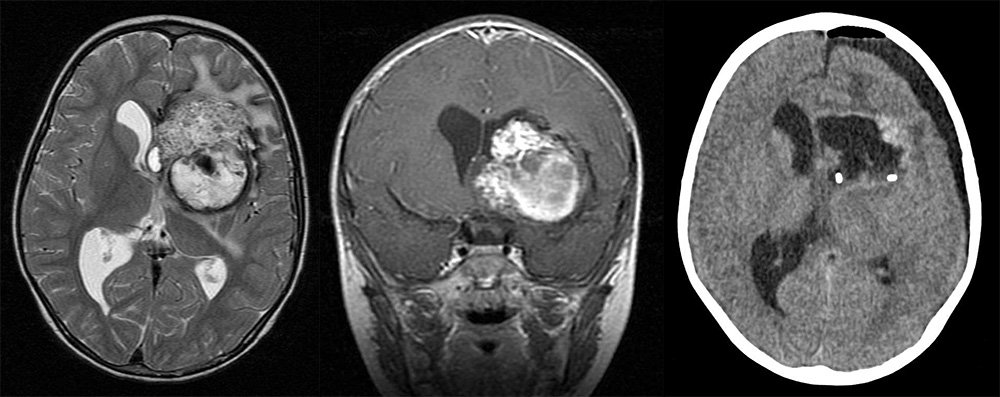

Мр картина венозной ангиомы левой гемисферы мозжечка - 96 фото